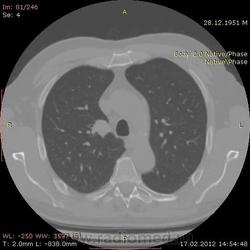

КТ.

В феврале 2012 года при очередном флюрографическом обследовании были обнаружены изменения в лёгких. По собственной инициативе было сделано КТ лёгких.

На первый взгляд - метастазы. А так, если родственник, искать выходы на МСКТ.

Согласен с Андреем Юрьевичем - наиболее вероятно - это метастазы...исключите первичное новообразование почки.